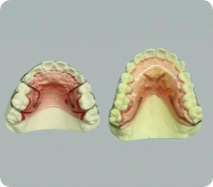

歯を失ってしまった時、もう一度自分の歯のように噛める喜びと美しさを取り戻せるのがインプラント治療です。 入れ歯やブリッジのように隣の健康な歯を削ったり、バネをかけて負担を強いることがないため、残っている大切な歯の寿命を延ばせるという大きなメリットもあります。